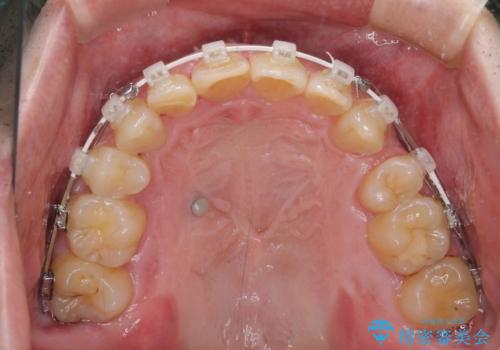

上顎歯列の叢生が著しかったため、上顎左右第一小臼歯2本を抜歯し、目立たないワイヤー装置にて治療を進めることとしました。

矯正治療後にはオーダーメイドタイプのオールセラミッククラウンを装着し、自然な口元に仕上がりました。